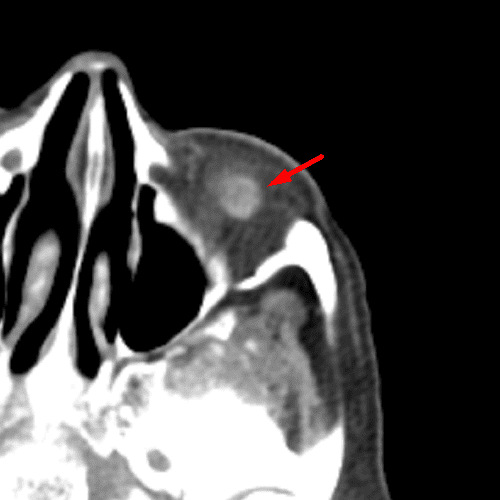

Optic Disc Drusen

Case 14